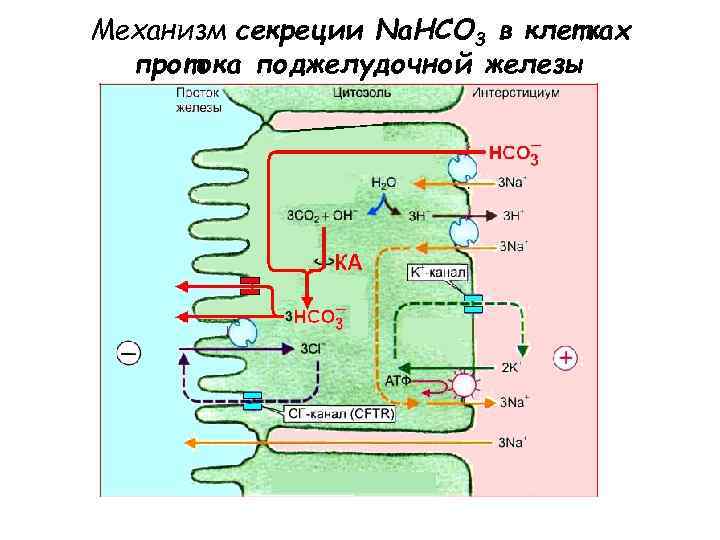

Механизм секреции Na. HCO 3 в клетках протока поджелудочной железы • НСОз- попадает в проток железы с помощью анионного обмена c Cl- (пассивный антипорт) • Параллельно подключённый Cl--канал обеспечивает рециркуляцию Cl--канал (CFTR — Cystic Fibrosis Transmembrane Conductance Regulator) • Необходим Na+/H+ антипорт через базолатеральную мембрану • Транспорт НСОз- зависит от Na+/К+-АТФазы на базолатеральной мембране • Жидкость в протоке заряжается отрицательно по отношению к интерстициальной (выход Cl- в просвет протока и проникновение К+ в клетку через базолатеральную мембрану), что способствует пассивной диффузии ионов Na+ в проток железы по межклеточным плотным контактам.

Механизм секреции Na. HCO 3 в клетках протока поджелудочной железы • НСОз- попадает в проток железы с помощью анионного обмена c Cl- (пассивный антипорт) • Параллельно подключённый Cl--канал обеспечивает рециркуляцию Cl--канал (CFTR — Cystic Fibrosis Transmembrane Conductance Regulator) • Необходим Na+/H+ антипорт через базолатеральную мембрану • Транспорт НСОз- зависит от Na+/К+-АТФазы на базолатеральной мембране • Жидкость в протоке заряжается отрицательно по отношению к интерстициальной (выход Cl- в просвет протока и проникновение К+ в клетку через базолатеральную мембрану), что способствует пассивной диффузии ионов Na+ в проток железы по межклеточным плотным контактам.

Механизм секреции Na. HCO 3 в клетках протока поджелудочной железы • Высокий уровень секреции НСО 3 - возможен, по всей видимости, потому что • НСО 3 - вторично активно транспортируется в клетку с помощью белка-переносчика, осуществляющего сопряженный транспорт Na+/ НСО 3 - (симпорт, белок-переносчик NBC, на первом рисунке не изображен) • Возможен выход НСО 3 - через люминальную мембрану через канал (второй механизм)

Механизм секреции Na. HCO 3 в клетках протока поджелудочной железы • Высокий уровень секреции НСО 3 - возможен, по всей видимости, потому что • НСО 3 - вторично активно транспортируется в клетку с помощью белка-переносчика, осуществляющего сопряженный транспорт Na+/ НСО 3 - (симпорт, белок-переносчик NBC, на первом рисунке не изображен) • Возможен выход НСО 3 - через люминальную мембрану через канал (второй механизм)